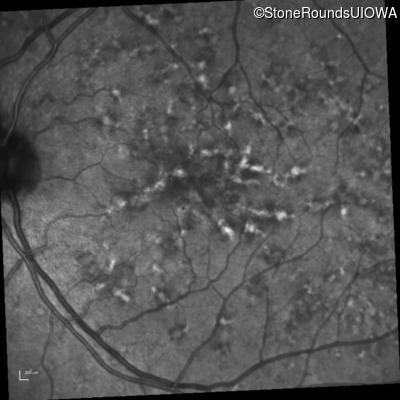

Blue Autofluorescence - Right - 20/20 -1 sc

Exemplar